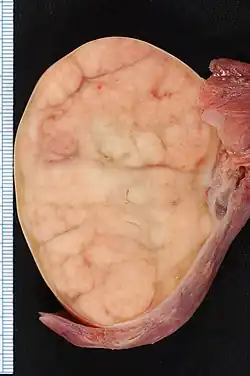

| 7.4 × 5.5-cm seminoma in a radical orchiectomy specimen. | |